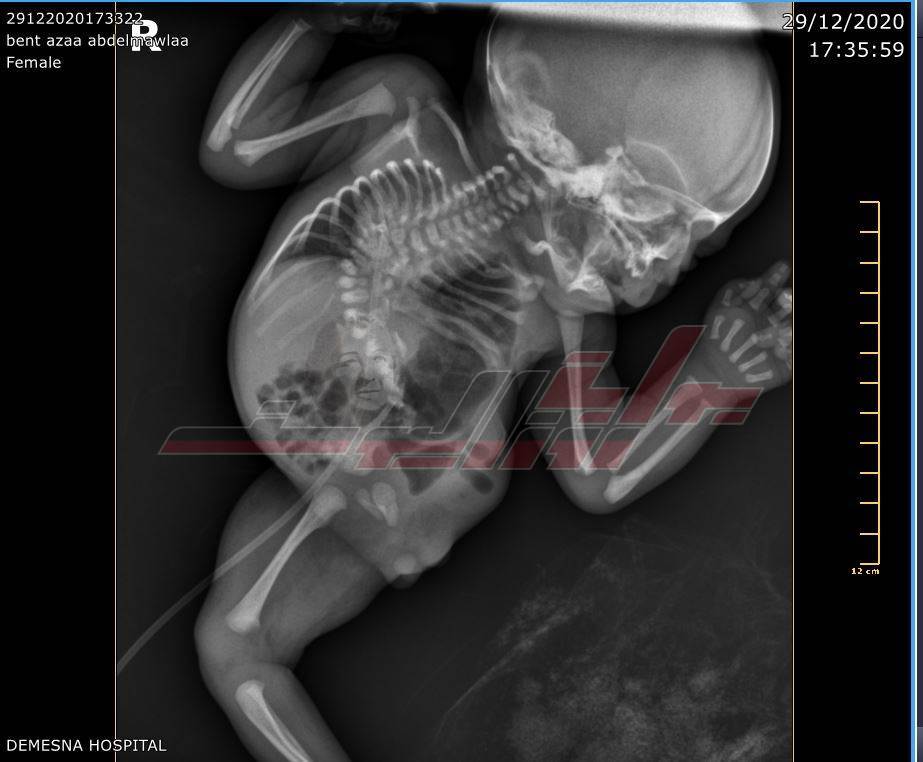

نجح فريق جراحة الأطفال بمستشفى دمسنا التخصصي للأطفال بمحافظة البحيرة، في إنقاذ حياة رضيعة عمرها يومان ووزنها كيلوجرام، عانت من عيوب خلقية متعددة، منها عدم وجود فتحة شرج ووجود القلب في الجهة اليمنى من صدرها وكانت تحتاج إلى جراحة عاجلة لخطورة حالته الصحية شكلت خطرًا كبيرًا على حياتها.

وقام الفريق الطبي المكون من الدكتور محمود عبد الهادي أستاذ جراحات الأطفال بطب الأزهر المشرف على وحدة الجراحات بمستشفى الأطفال التخصصي بالبحيرة والدكتور أحمد النعناعي أخصائي التخدير، والفريق الطبي في إجراء العملية الجراحية.